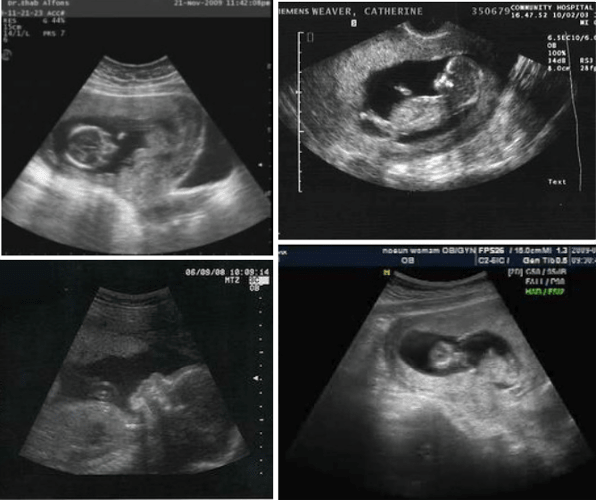

16 week ultra sound gender reveal | Medical ultrasound, 16 weeks …